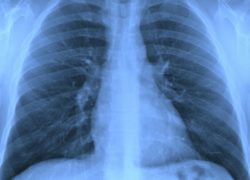

What is Mesothelioma?

Mesothelioma is a rare form of cancer in which malignant (cancerous) cells are found in the mesothelium, a protective sac covering most of the body’s internal organs. Most people who develop this disease have worked on jobs where they inhaled asbestos particles. Read more…